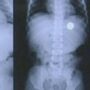

Недавно Балаково.Онлайн писал о том, что в Балаково двое малышей проглотили инородные предметы.